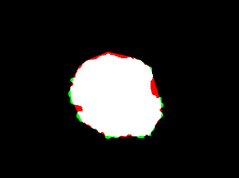

Skin lesion segmentation is one of the crucial steps for an efficient non-invasive computer-aided early diagnosis of melanoma. This paper investigates how color information, besides saliency, can be used to determine the pigmented lesion region automatically. Unlike most existing segmentation methods using only the saliency in order to discriminate against the skin lesion from the surrounding regions, we propose a novel method employing a binarization process coupled with new perceptual criteria, inspired by the human visual perception, related to the properties of saliency and color of the input image data distribution. As a means of refining the accuracy of the proposed method, the segmentation step is preceded by a pre-processing aimed at reducing the computation burden, removing artifacts, and improving contrast. We have assessed the method on two public databases, including 1497 dermoscopic images. We have also compared its performance with classical and recent saliency-based methods designed explicitly for dermoscopic images. The qualitative and quantitative evaluation indicates that the proposed method is promising since it produces an accurate skin lesion segmentation and performs satisfactorily compared to other existing saliency-based segmentation methods.